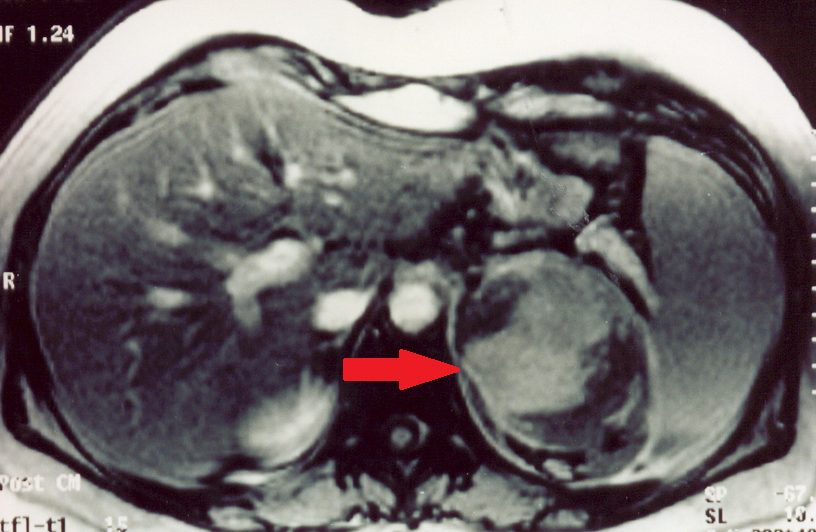

CT scan, 13 years after the initial identification of a non-functional incidentaloma of the right adrenal gland. Presence of a heterogeneous tumor – adrenocortical carcinoma of the right adrenal gland (Courtesy Dr. V. Penopoulos)